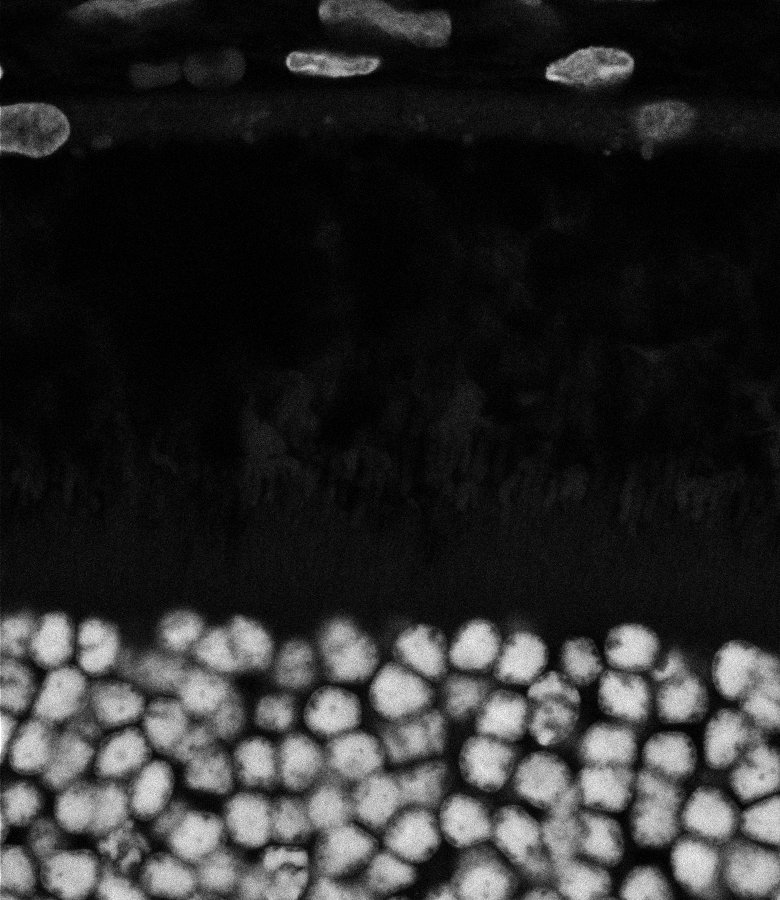

Healthy Eye

Overview 1

Blast Eye